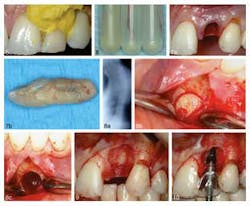

An innovative procedure, utilizing a single incision for access and localized antibiotics to treat infection, is being introduced that will enable immediate implantation with a bone graft harvested from a portion of the patient’s own lower jaw. A case study in the Journal of Oral Implantology provides an in-depth analysis of this new approach for immediate treatment and implantation of an infected area.RELATED READING |Study finds that shorter waiting time between dental procedures is adequate In oral implant surgery, immediate implantation of the area of interest is preferred, as delaying the procedure can have a negative effect on the structure of hard and soft tissues. Frequently, required surgeries coincide with oral infection and surgeons prefer to wait until the infection is resolved before performing the reconstructive implant surgery. This time-lapse in placement of reconstructive bone grafts and the delayed implant placement may compromise the final esthetic result.RELATED READING |Improved dental implant surface and hygiene boost restoration success In the case study, a 43-year-old female presenting with a front-tooth infection of seven-months duration underwent a root canal and antibiotics. When symptoms persisted, tooth removal was recommended. Despite the presence of infection, the patient was able receive a bone graft harvested from the symphysis of her mandible. Application of localized antibiotics was used to treat the infection. Three years' postoperatively, the patient presented with no negative effects.

Regarding recovery from oral surgery, immediate implantation is critical to: • Preserving the structure of the soft and hard tissue • Shortening the recovery period • Prevention of future corrective surgeries Grafting procedures using bone from the patient’s own body has been the gold standard for years; therefore, it is a natural progression for oral implantation to follow suit.Full text of the article, “3 Year Follow Up of a Single Immediate Implant Placed in an Infected Area: A Clinical Report of a Novel Approach for the Harvesting Autogenous Symphysis Graft,” Journal of Oral Implantology, Vol. 40, No. 2, 2014, is available here. For more information about the Journal of Oral Implantology, visit their website.